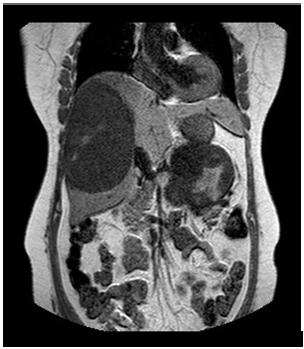

CT scan abdomen revealed Peripheral–sub capsular- large right hepatic heterogeneous well-defined lesion is seen measuring 13x9cm showing peripheral wall enhancement & heterogeneous internal enhancement noted in arterial phase and persist in venous with internal vessels seen (Figure 3). Complete wash out in delayed image noted. Other small satellite hypo attenuated lesion is seen medially measuring 1.4x0.9cm showing heterogeneous pattern. Other large lobulated heterogeneous left suprarenal lesion is seen measuring 12x7cm showing cystic/necrotic anterolateral portion and heterogeneous enhancement (Figure 4). This mass is seen separated from the left kidney & indenting the displacing the pancreatic tail anteriorly. The left adrenal gland is not seen. Routine blood tests were unremarkable.

Figure 3 CT Scan Abdomen: Reported a liver mass of about 13x9 cm size.

Figure 4 MRI Abdomen: Reported a liver lesion of 12.4x 9cm & adrenal lesion 12 x 8.7cm size.